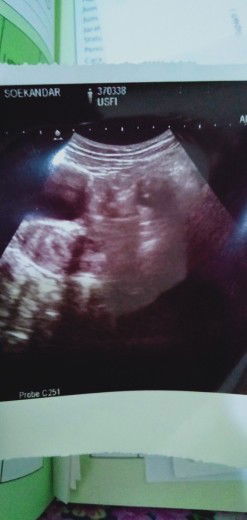

hamil 4 Minggu 3hari

Bunda.. aq Senin kemarin USG.. hasilnya gini.. Dedeknya kecil bgt.. apa uk segitu normal.. maklum.. hamil kedua .. tp yg pertama baru tau hamil pas udh keguguran.. jd kurang pengalaman.. makasih bund